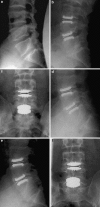

A retrospective clinical-radiological study to evaluate the long-term outcome after artificial disc replacement was performed. The objective is to investigate long-term results after implantation of a modular type artificial disc prosthesis in patients with degenerative disc disease (DDD). Total disc replacement (TDR) is a surgical procedure intended to save segmental spinal function, and thus replace spondylodesis. Short-term results are promising, whereas long-term results are scarce. The Charité TDR is the oldest existing implant, therefore, the longest possible follow-up is presented here. Seventy-one patients were treated with 84 Charité TDRs types I-III. Indication for TDR was moderate to severe DDD. Fifty-three patients (63 TDRs) were available for long-term follow-up of 17 years. Evaluation included Oswestry disability index, visual analog scale, overall outcome score, plain and extension/flexion radiographs. Implantation of Charité TDR resulted in a 60% rate of spontaneous ankylosis after 17 years. No significant difference between the three types of prostheses was found concerning clinical outcome. Reoperation was necessary in 11% of patients. Although no adjacent segment degeneration was observed in the functional implants (17%), these patients were significantly less satisfied than those with spontaneous ankylosis. TDR, nowadays, is an approved procedure. Proof that long-term results of TDR implantation in DDD are at least as good as fusion results is still missing.